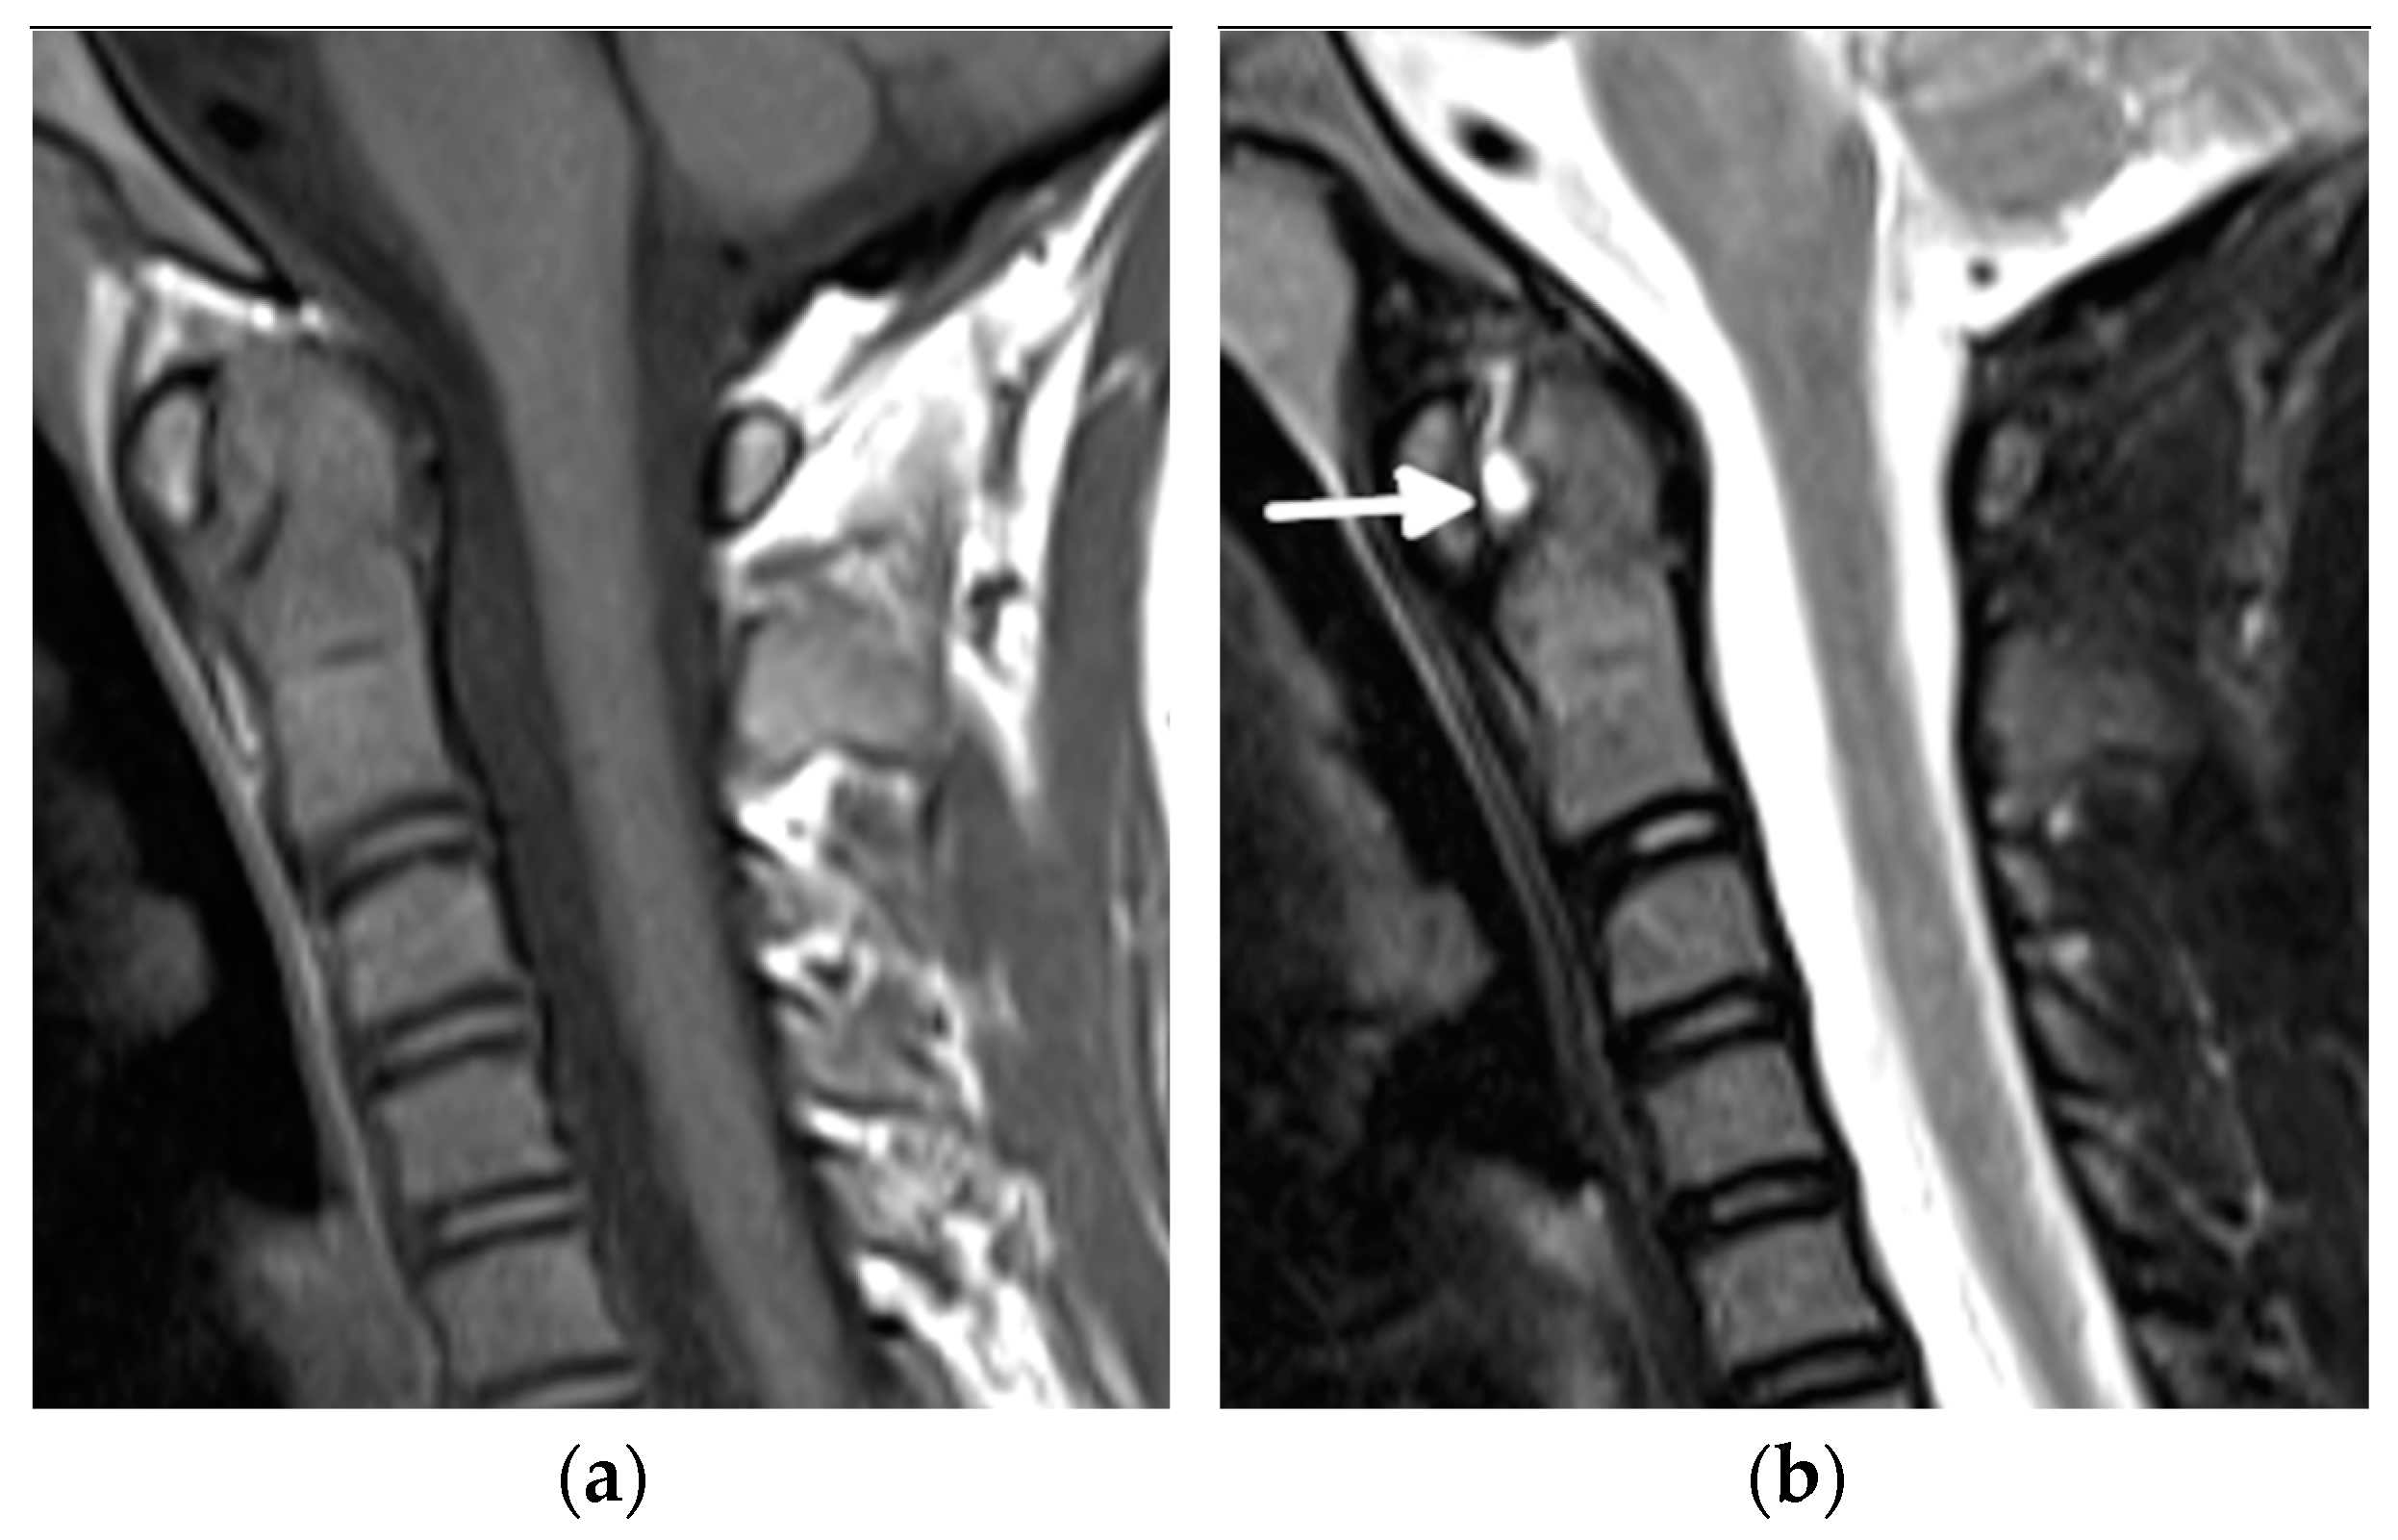

- Laiho, K.; Savolainen, A.; Kautiainen, H.; Kekki, P.; Kauppi, M. The cervical spine in juvenile chronic arthritis. Spine J. 2002, 2, 89–94. [Google Scholar] [CrossRef]

- Hospach, T.; Maier, J.; Müller-Abt, P.; Patel, A.; Horneff, G.; von Kalle, T. Cervical spine involvement in patients with juvenile idiopathic arthritis—MRI follow-up study. Pediatr. Rheumatol. Online J. 2014, 12, 9. [Google Scholar] [CrossRef]

- Ključevšek, D.; Emeršič, N.; Toplak, N.; Avčin, T. Clinical and MRI outcome of cervical spine lesions in children with juvenile idiopathic arthritis treated with anti-TNFα drugs early in disease course. Pediatr. Rheumatol. Online J. 2017, 15, 38. [Google Scholar] [CrossRef]

- Munir, S.; Patil, K.; Miller, E.; Uleryk, E.; Twilt, M.; Spiegel, L. Juvenile idiopathic arthritis of the axial joints: A systematic review of the diagnostic accuracy and predictive value of conventional MRI. AJR Am. J. Roentgenol. 2014, 202, 199–210. [Google Scholar] [CrossRef]

- Kotecki, M.; Gietka, P.; Posadzy, M.; Sudoł-Szopińska, I. Radiographs and MRI of the Cervical Spine in Juvenile Idiopathic Arthritis: A Cross-Sectional Retrospective Study. J. Clin Med. 2021, 10, 5798. [Google Scholar] [CrossRef]